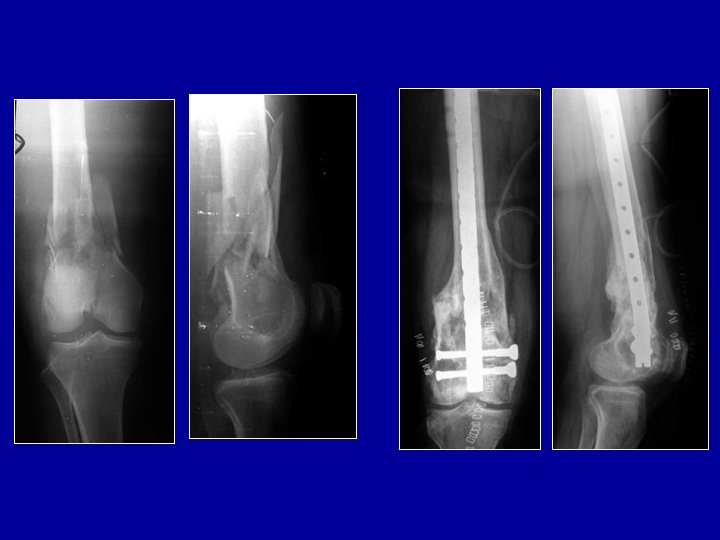

Ostéosynthèse du tibia par plaque vissée Plaque sur la corticale externe ou interne

Indication des plaques : les fractures métaphysaires

Indication des plaques : les fractures métaphysaires Manuel AO

Exemple d’ostéosynthèse mixte : clou verrouillé pour le tibia et plaque pour le péroné